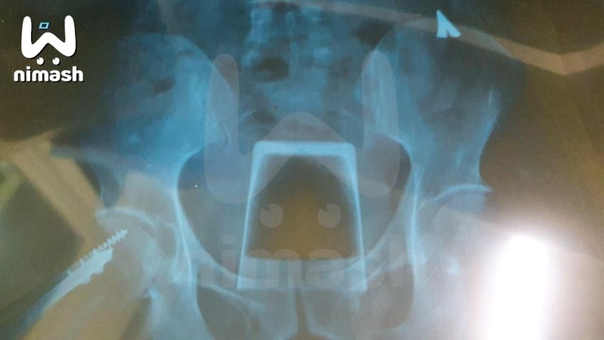

Врачи обнаружили в жителе Нижнего Новгорода хрустальный стакан

То, что было дальше, больно, поэтому не принимайте близко к сердцу. Потенциального пациента увезли в реанимацию и сделали рентген.

Под удивлёнными взглядами бригады медиков перевели в операционную, чтобы помочь избавиться от всего лишнего в жизни.